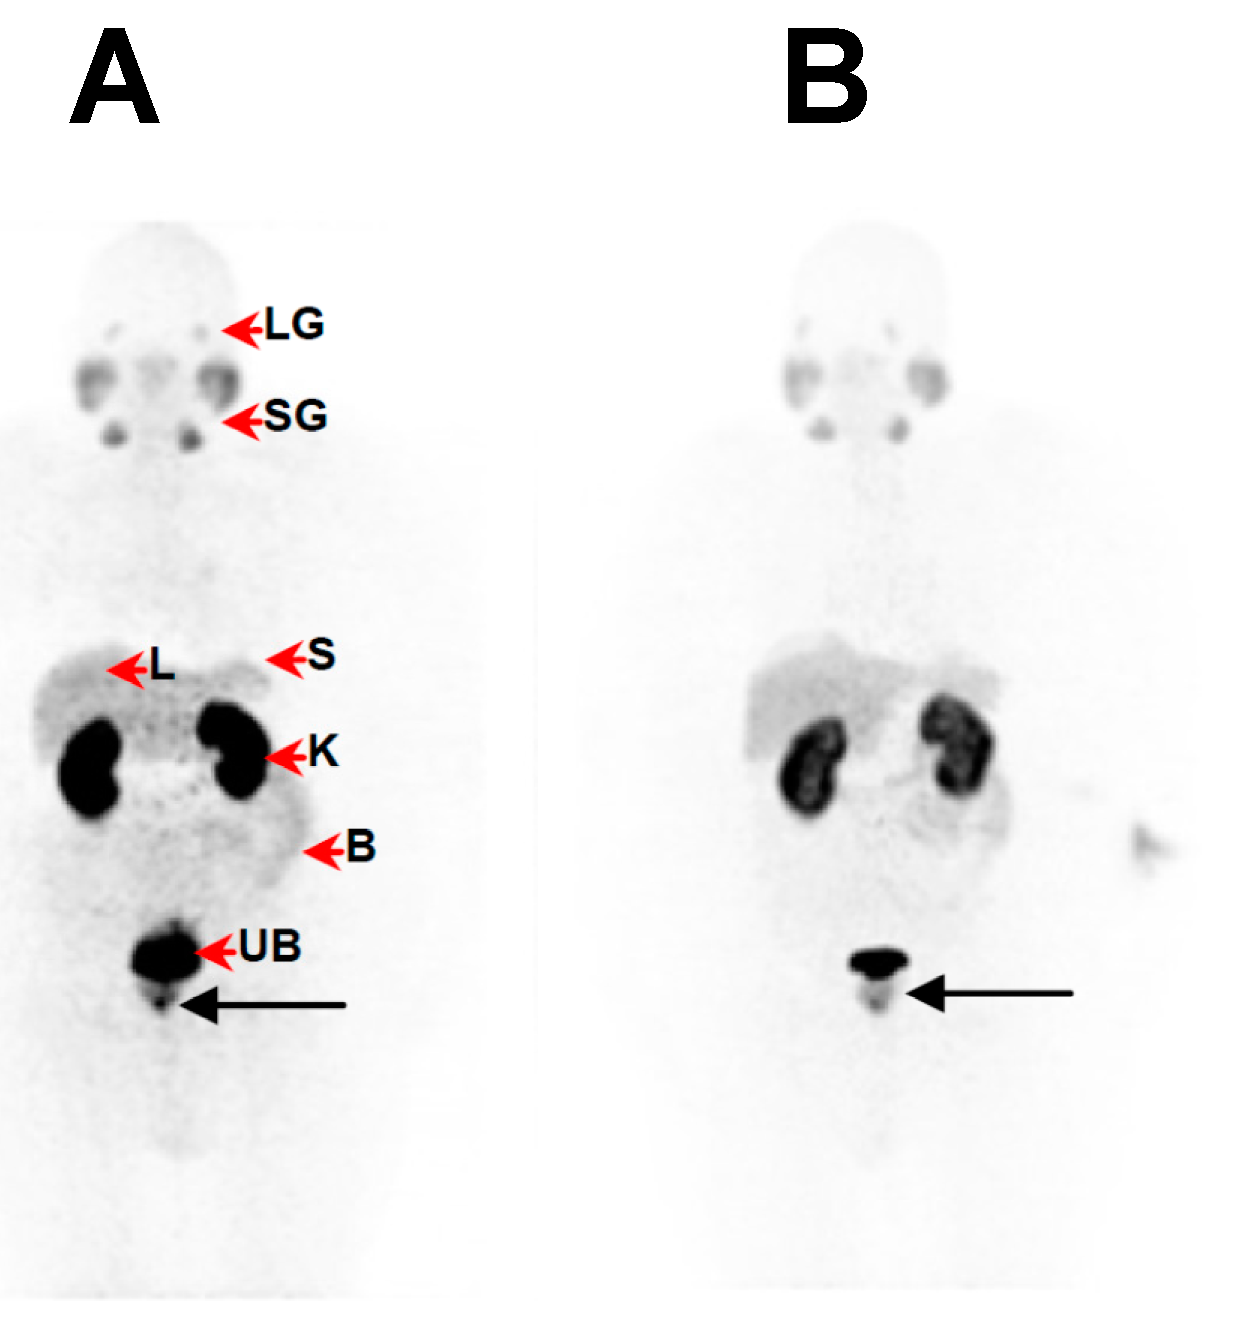

2.5. Clinical PET/CT—68Ga-DKFZ-PSMA-11 Kit Performance in Prostate Cancer Patients

Image Acquisition, Reconstruction and Analysis